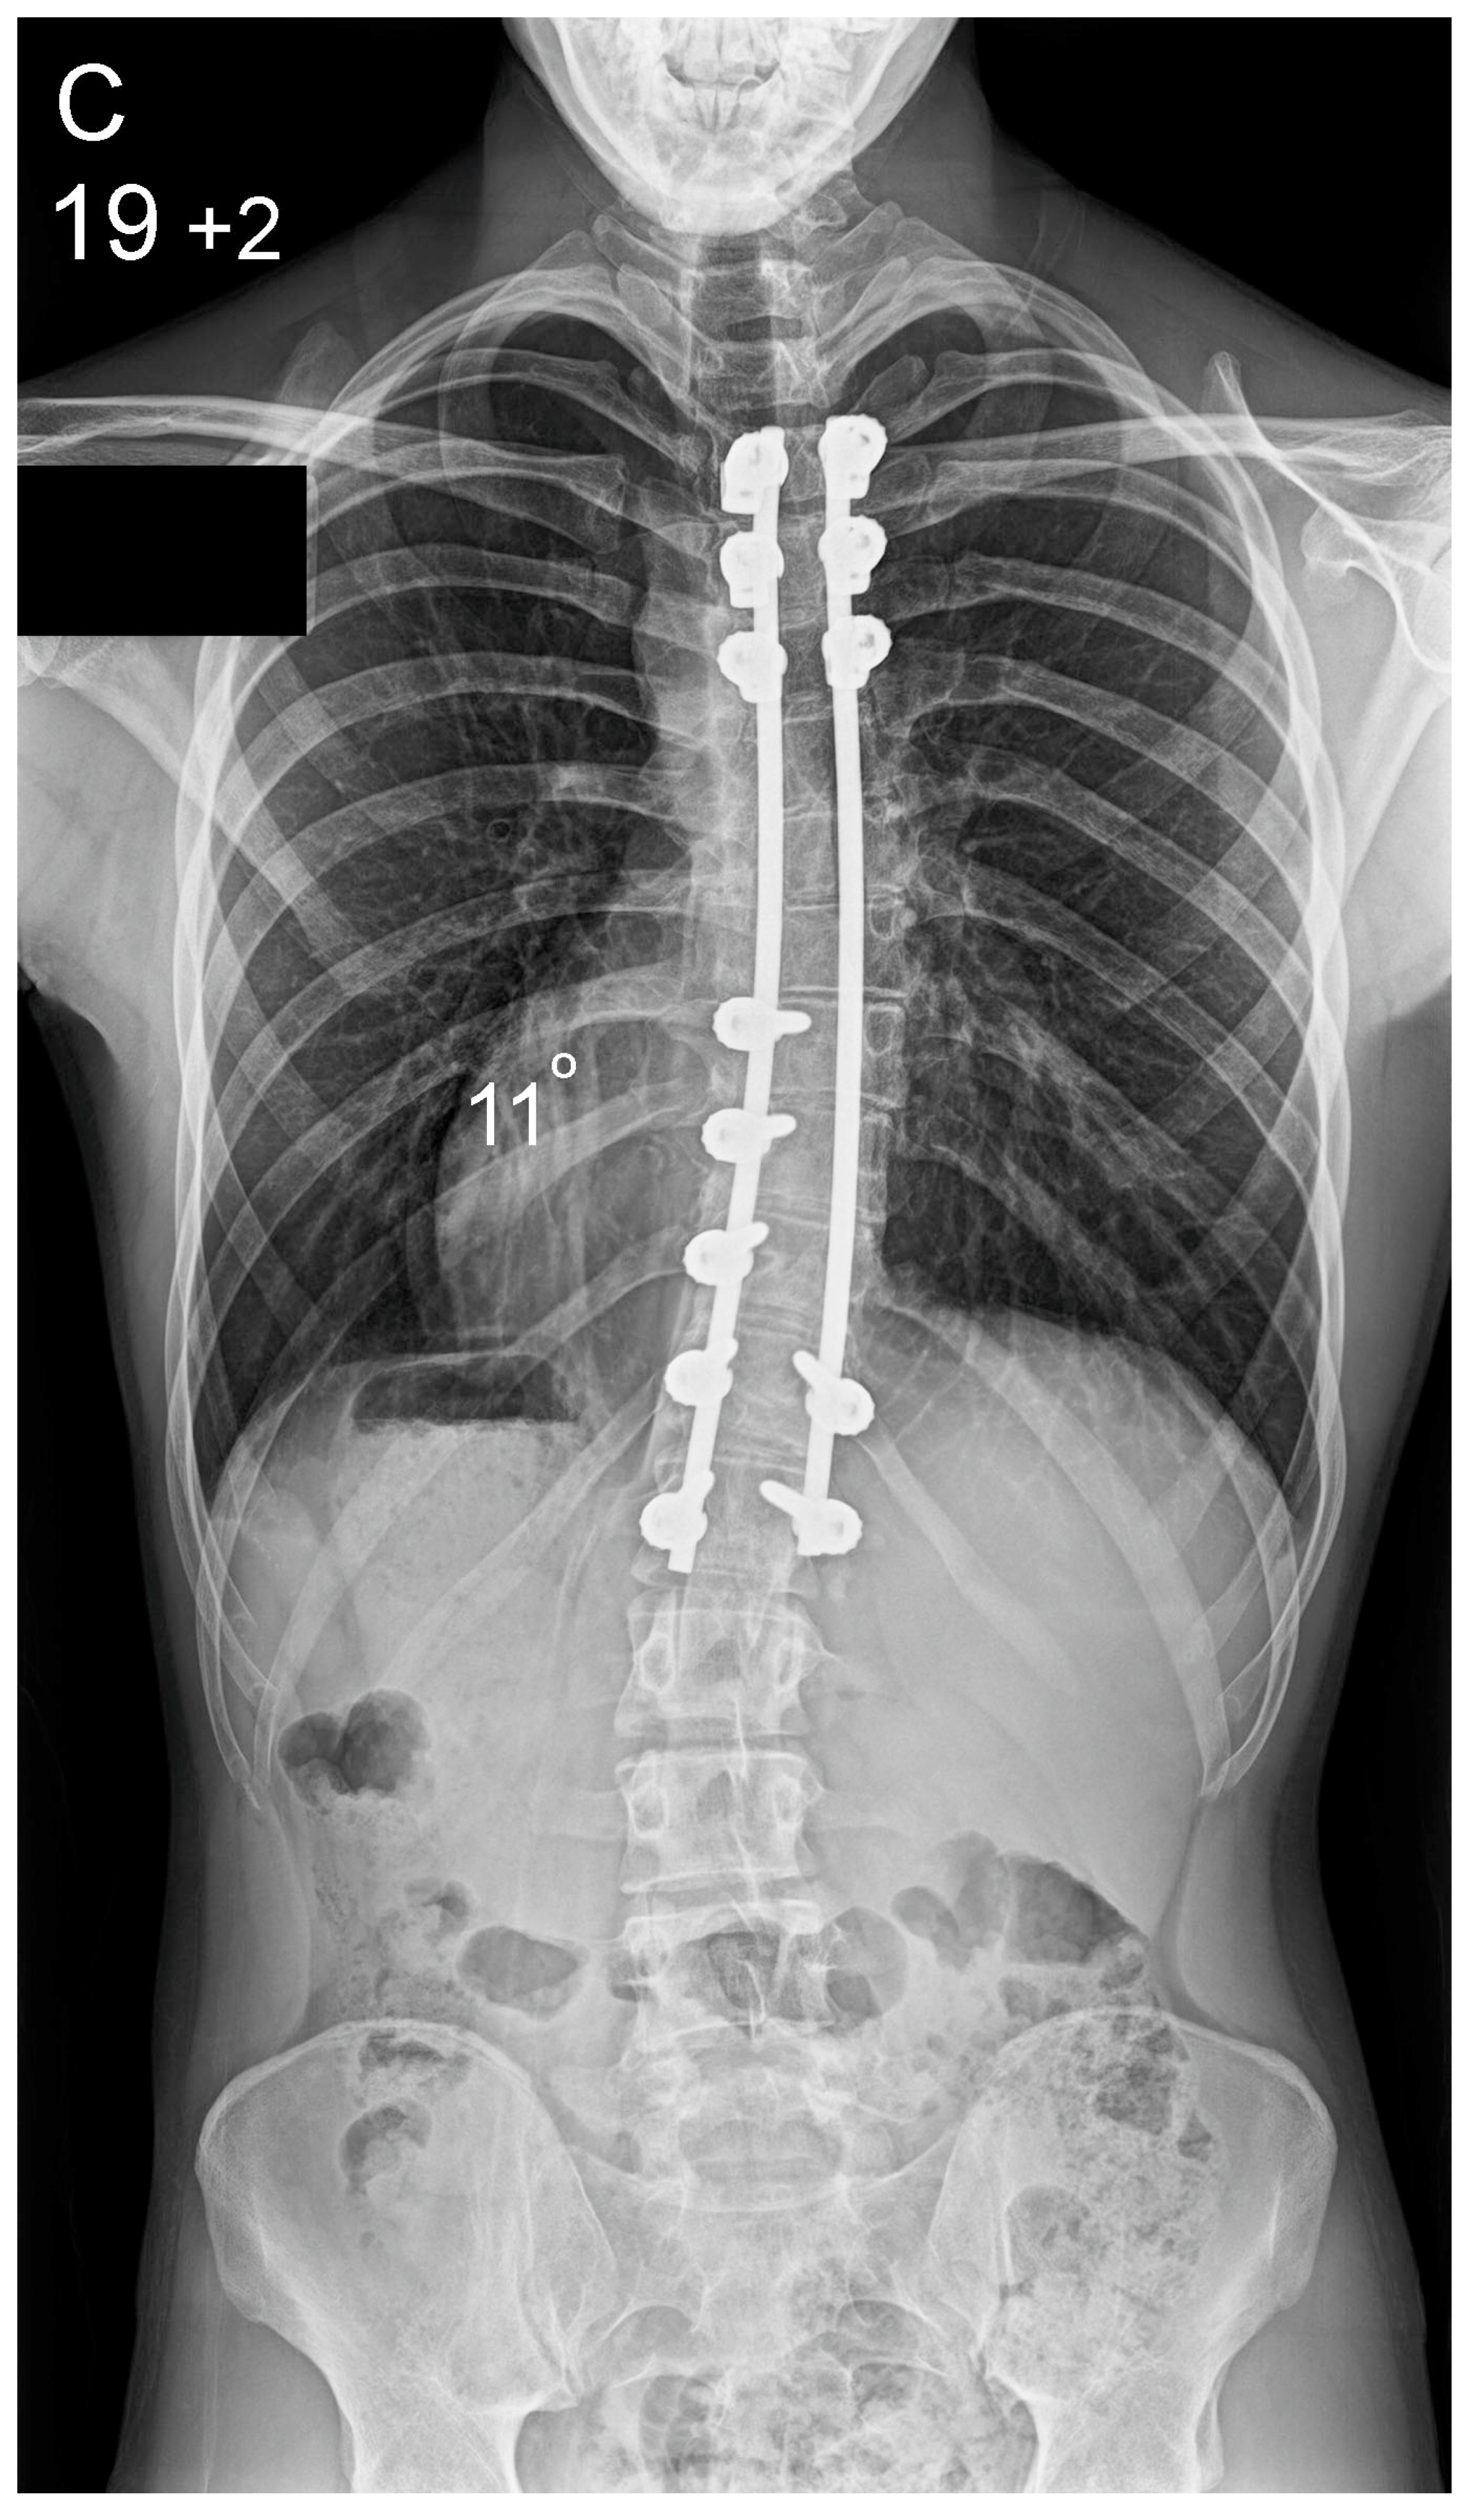

Figure 2.

Patient aged 15 years and 9 months with a right thoracic AIS producing thoracic translocation and listing of the trunk to the right, as well as a lordotic thoracic spine causing spinal penetration into the chest, partial bronchial obstruction and right lower lobe atelectasis (A,B). The patient underwent posterior scoliosis correction using the HS technique which restored segmental and global coronal/sagittal spinal balance at latest follow-up (age 19 years and 2 months) into adult life (C,D). Clinical photographs demonstrate excellent correction of the coronal deformity and associated rib hump after scoliosis surgery (E–H).